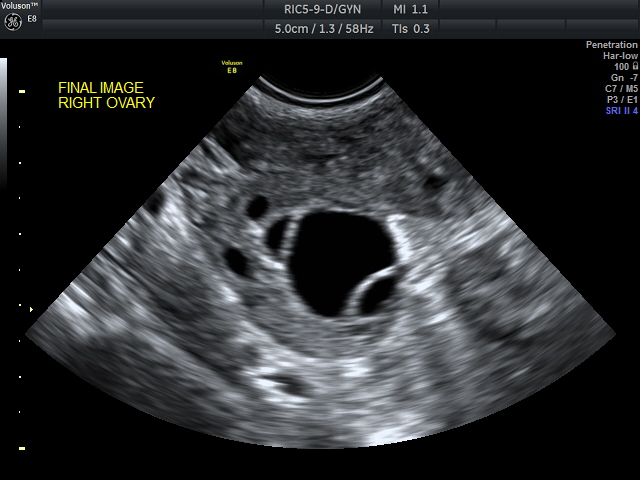

The fertility specialist will most likely organise an ultrasound scan at this stage to check the following.

1. If the female partner is ovulating (releasing an egg every 4-6 weeks). This is assessed through a series of blood tests checking hormones, and can be confirmed later using an ultrasound scan.